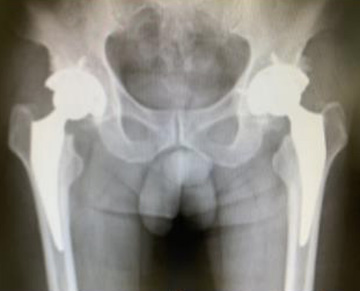

• 手術後